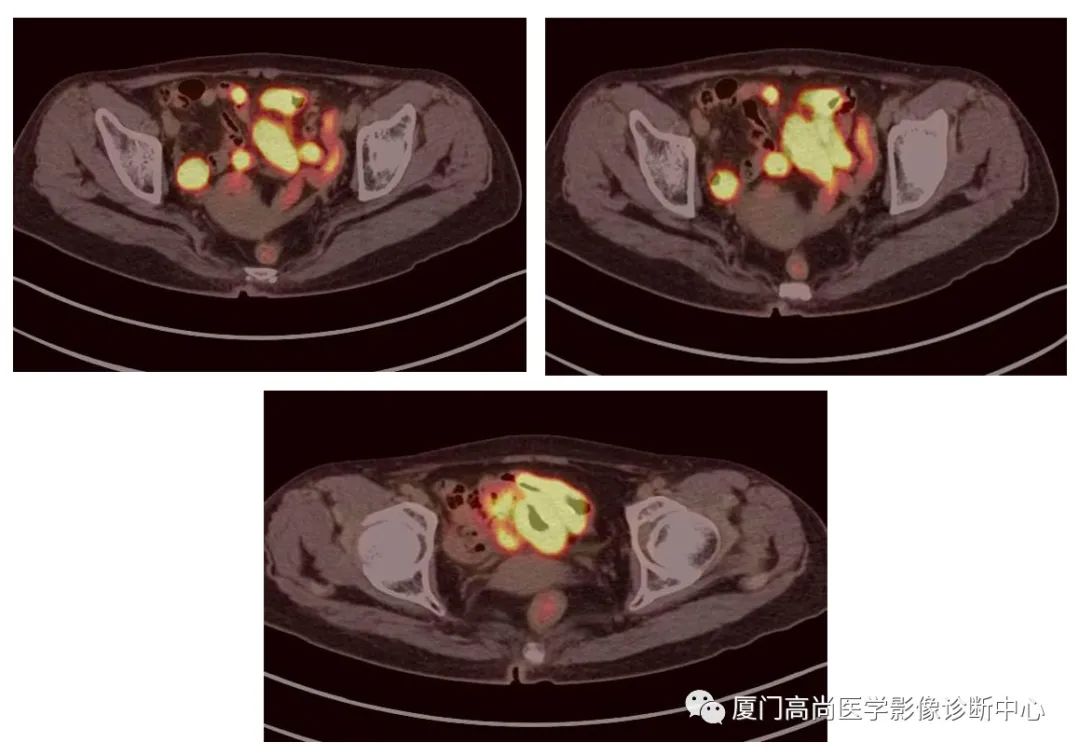

病例1:某男士,36歲,半年前摔傷,當(dāng)時無大礙,近幾個月來腰腿痛,并逐漸加重,消瘦10多斤。MRI檢查發(fā)現(xiàn)腰椎、骨盆 骨質(zhì)異常信號,查血各項腫瘤標(biāo)記物正常,因診斷不清而來做PET/CT檢查

淋巴瘤在骨骼、肝臟、脾臟、淋巴結(jié)表現(xiàn)

肝臟、脾臟、骨骼淋巴瘤病灶

PET/CT發(fā)現(xiàn) :全身多發(fā)淋巴結(jié)腫大,F(xiàn)DG攝取增高;肝臟、脾臟多發(fā)低密度結(jié)節(jié), FDG攝取增高;雙側(cè)扁桃體腫大,F(xiàn)DG攝取增高;全身多處骨骼破壞,F(xiàn)GD攝取增高;上述考慮為淋巴瘤

經(jīng)淋巴結(jié)穿刺活檢 :病理診斷為彌漫大B細(xì)胞淋巴瘤